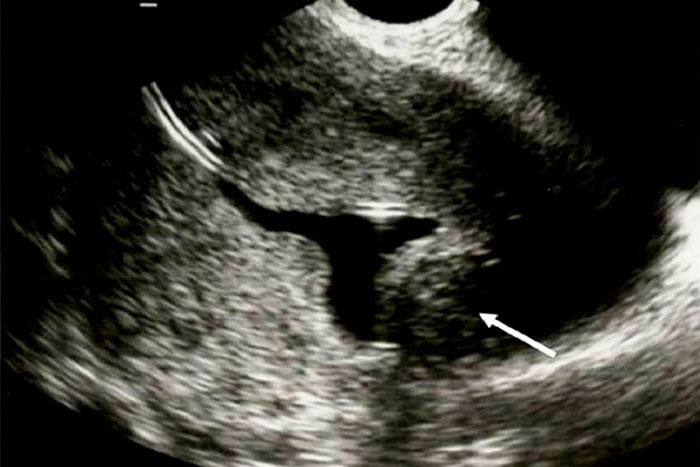

رویت ناچ بیشتر از یک سانتی متر در فوندوس رحم مطرح کننده رحم دو شاخ می باشد.هر دو شاخ در ظاهر و اندازه قرینه هستند و ارتباط کامل بین هر دو شاخ وجود دارد.در هیستروسونوگرافی دو آندومتر دیده می شود. (8،7)

در هیستروسونوگرافی فوندوس رحم کاملا صاف و یا با کمی تحدب دیده می شود ممکن است تقعر کمتر از 1 سانتی متر وجود داشته باشدو در رحم سپتوم دار دو آندومتر دیده می شود. در مواردیکه سپتوم کامل است سپتوم تا ext. os ادامه می یابد و ممکن است در هیستروسکوپی نمایی شبیه رحم دو شاخ داشته باشد.